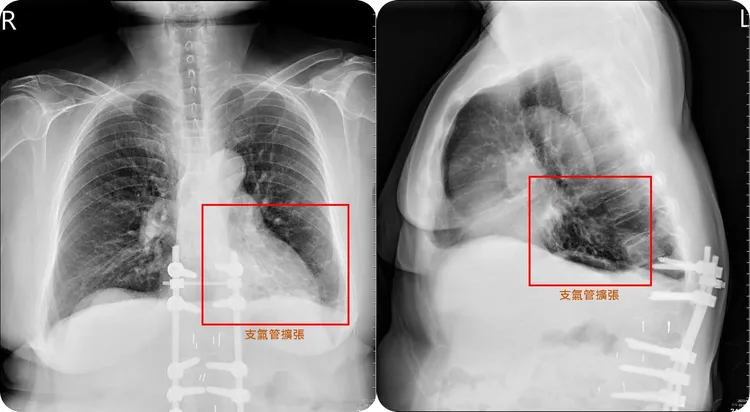

患者左下肺部的支氣管嚴重擴張,出現各種不適症狀。亞大附醫提供

謝逸安指出,支氣管擴張症的中文翻譯過於簡化,往往會讓病人聽到的當下摸不著頭緒,簡單來說,支氣管擴張症主要是肺部支氣管壁因為先天(基因)或後天的原因導致結構破壞,小支氣管失去彈性彎曲及擴張,形成永久不可逆性的擴張,導致痰液容易堆積,而支氣管壁上負責執行痰液清潔的纖毛,也因反覆發炎遭到破壞而雪上加霜。

謝逸安表示,這類病人最常見的症狀就是咳嗽不止,不僅早晨會咳出又髒又濃的黃痰,甚至還有血痰、呼吸困難及胸痛等併發症,呼吸道感染頻率也會隨之增加,若是長期未治療,還會導致食慾減退及容易疲倦,增加呼吸衰竭的風險。